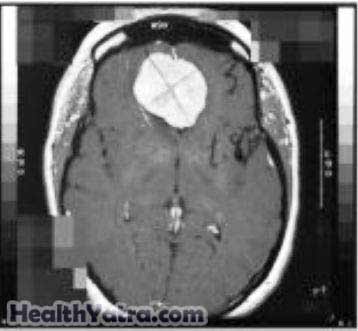

Images of your head may need to be viewed. This can be done with:

- CT scan

- MRI scan